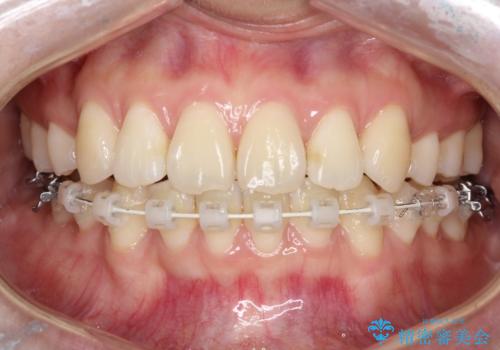

- 出っ歯、ガタツキ、噛み合わせが気になるとのことで来院された患者様です。

小臼歯を抜歯することでスペースを作り、前歯を下げて口元を下げ、Eラインを改善する治療方針としました。

表側のワイヤーは見た目が気になるとのことで、上の歯だけ裏側に付くハーフリンガルという装置で治療を行いました。